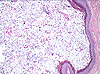

CASO N° 2 (Dr. Elismauro e Dr. Delgado)

Paciente do gênero masculino, 85 anos de idade, apresenta um aumento de volume na maxila esquerda.